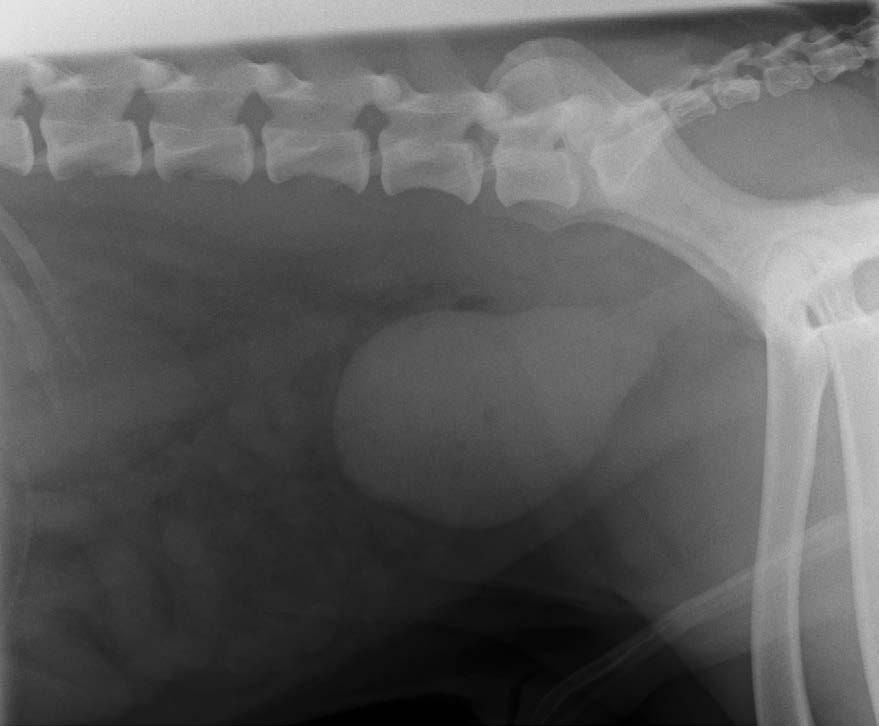

Radiopaque Bladder Stones Dog . Urinary stones (urolithiasis) are a common condition responsible for lower urinary tract disease in dogs and cats. Hence these stones are commonly called infection stones. The most common signs of bladder stones in dogs are: Straining to urinate (called dysuria). Blood in the urine (called hematuria) and; Stones vary from radiographically invisible to mildly radiopaque. Most dogs with cystine stones are intact males and form their first stone within the first two years of life. Most stones are radiopaque, meaning they show up on the radiographic film as obvious white objects within the urinary bladder.

The most common signs of bladder stones in dogs are: Straining to urinate (called dysuria). Blood in the urine (called hematuria) and; Most dogs with cystine stones are intact males and form their first stone within the first two years of life. Most stones are radiopaque, meaning they show up on the radiographic film as obvious white objects within the urinary bladder. Stones vary from radiographically invisible to mildly radiopaque. Hence these stones are commonly called infection stones. Urinary stones (urolithiasis) are a common condition responsible for lower urinary tract disease in dogs and cats.